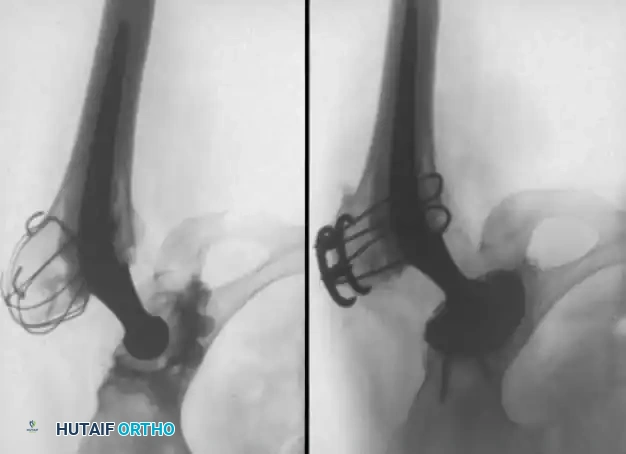

Image

1. Component Insertion: Impact the trial shell to confirm stability and coverage. Once confirmed, impact the final porous-coated (uncemented) acetabular shell. Ensure a rigid press-fit. Supplemental screws may be used in the safe zone (posterosuperior quadrant) if initial stability is questionable.